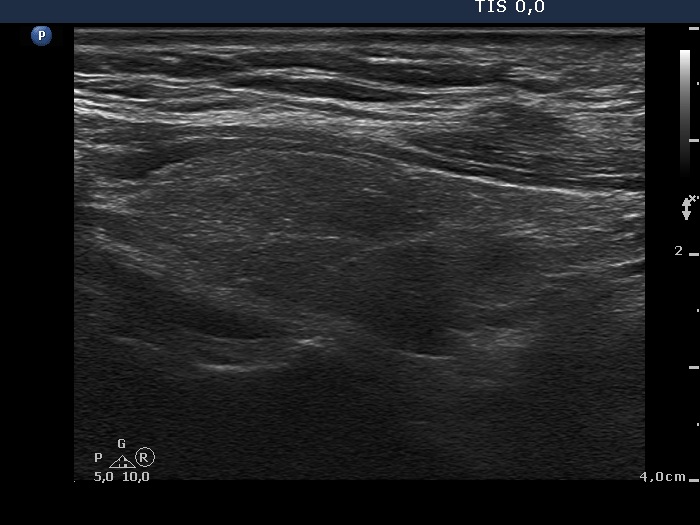

The operated thyroid - Case 8. A patient after near total lobectomy

Six weeks after surgery (ultrasonographic picture 2)

Right lobe, longitudinal scan. Note fibrotic changes.